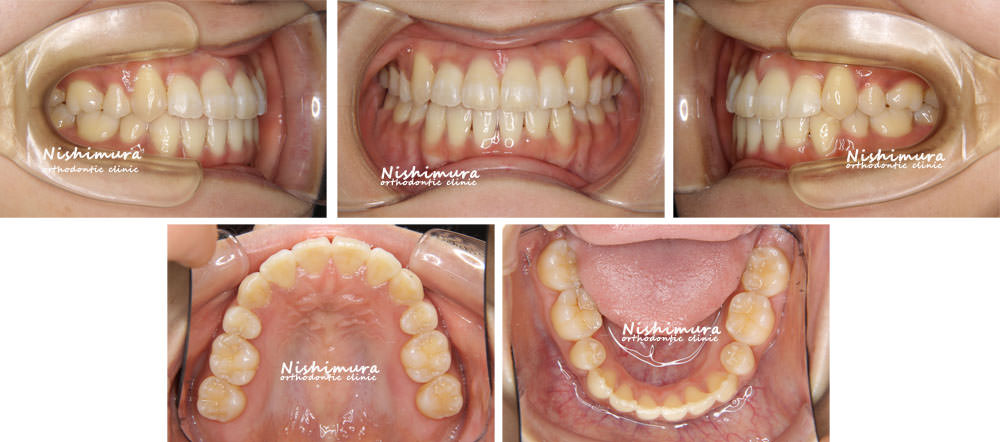

治療前

治療前の写真

治療後

治療後の写真

歯列が前後に凸凹、八重歯

叢生、上顎犬歯の低位唇側転位(八重歯)